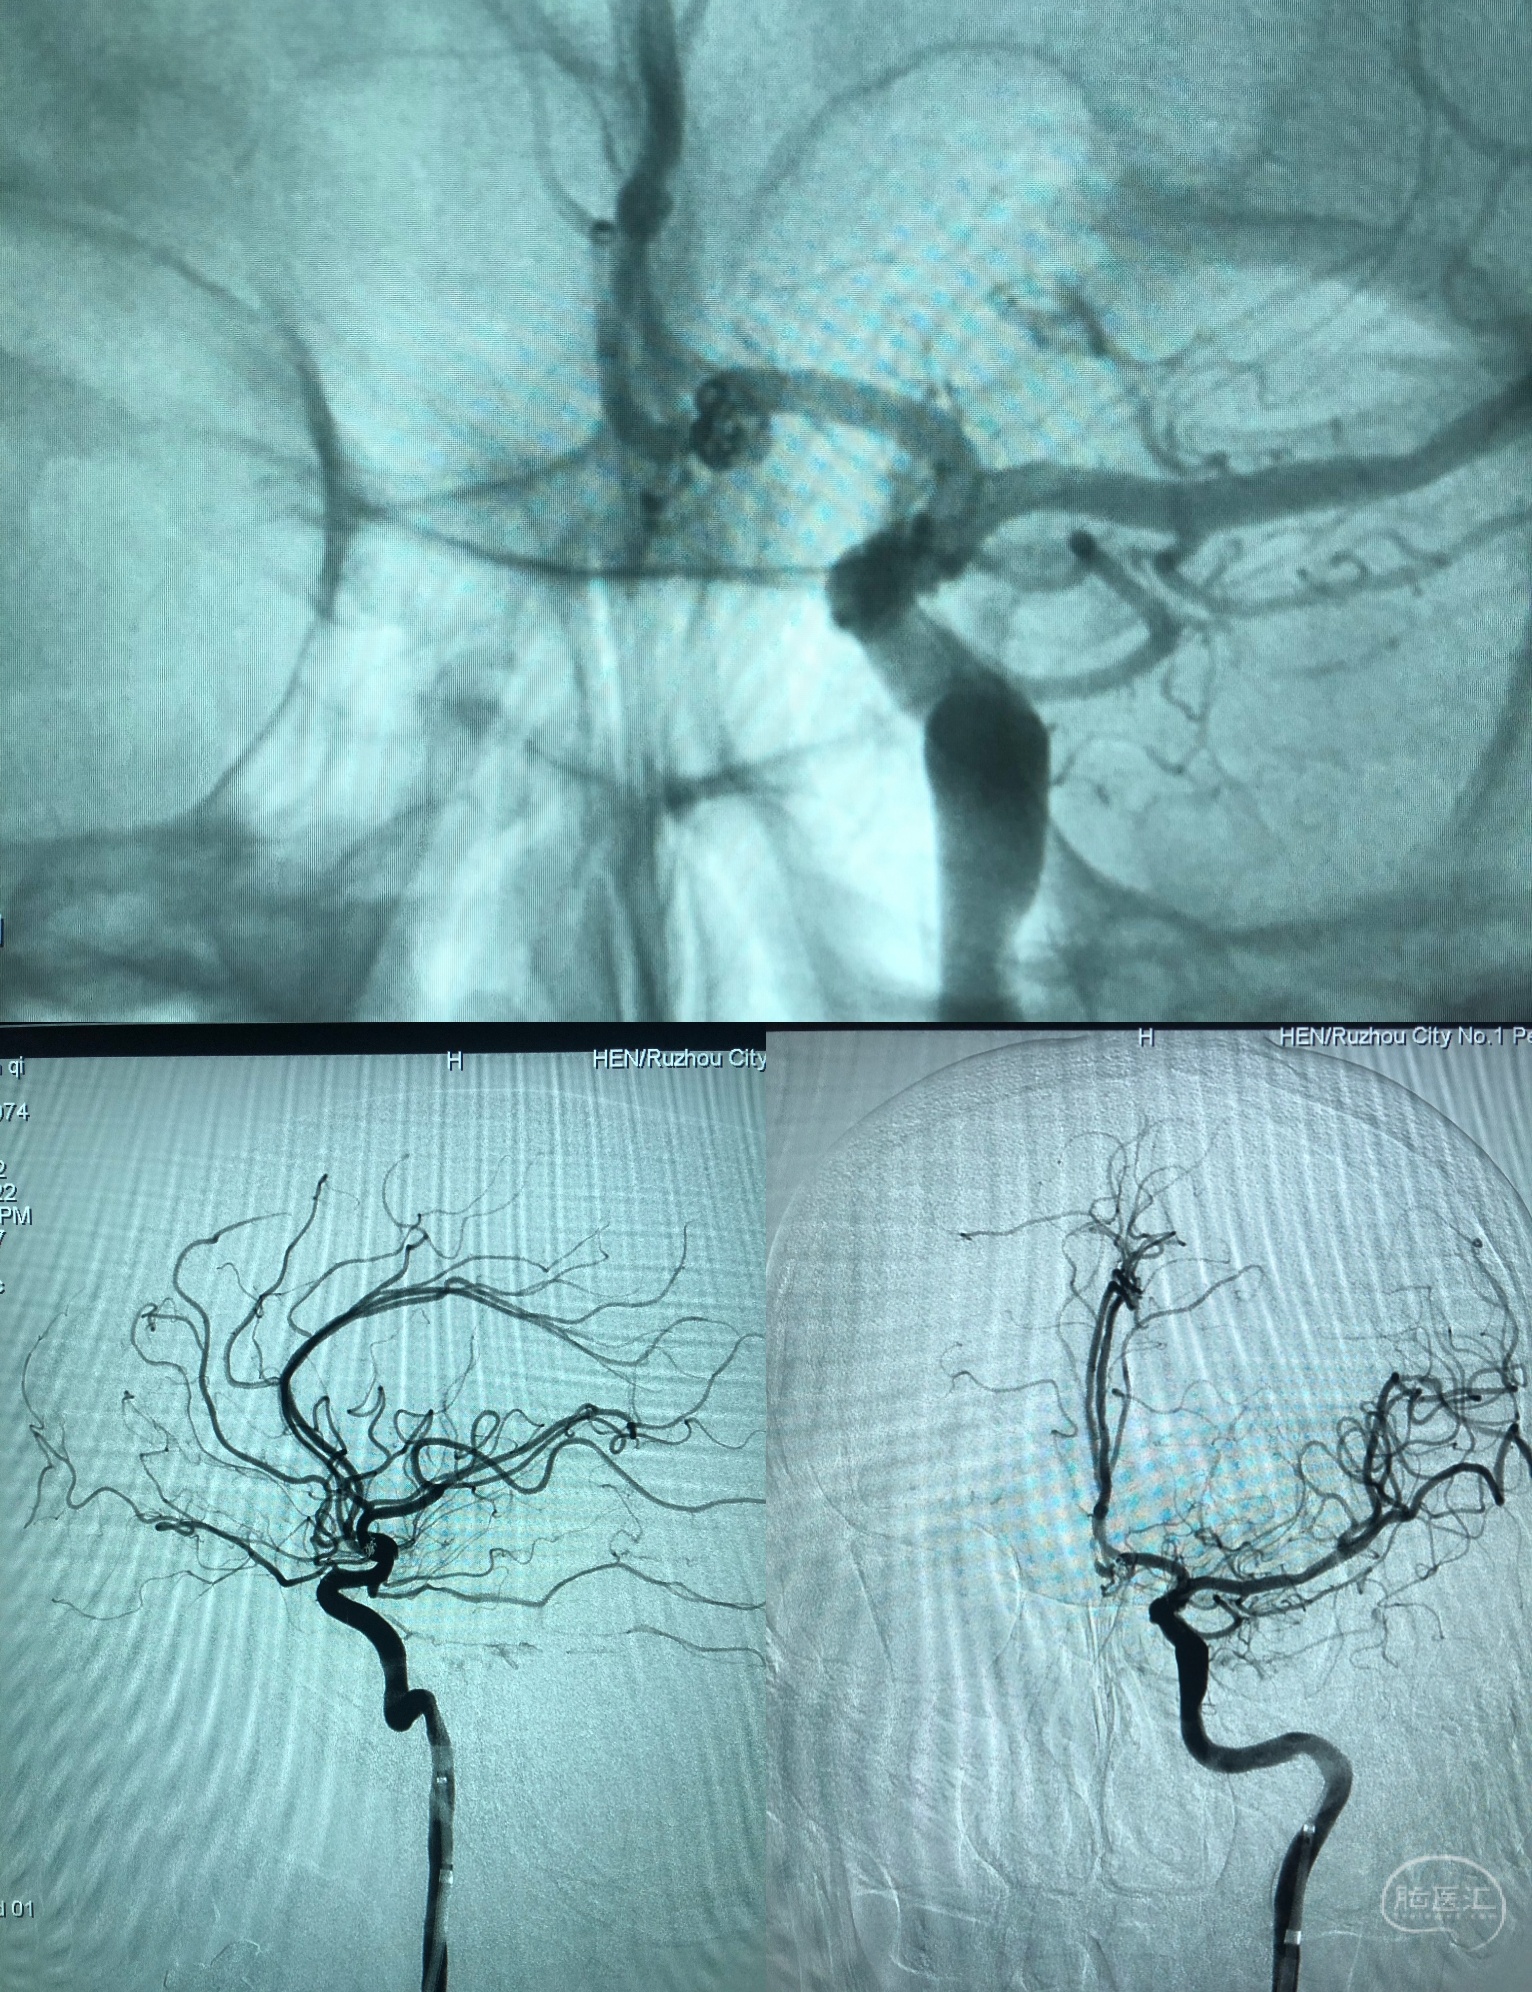

造影:右侧A1存在。

通路:8FGD+6FNavien115。GD置于C2段,Navien置于眼动脉段。

ASAHI微导丝头段机械塑形J形。支架微导管Headway17置于左侧A3段备放LEObaby支架。

栓塞微导管Headway17(30公分软头)热塑性打C,头端约5mm塑的比较弯。微导管顺利到位。

填塞过程

计算:动脉瘤直径:2.98*2.38,瘤颈1.71mm 预计填入弹簧圈长度:2.98*2.38*1.26大约9厘米。

实际:首枚圈2.5*4 3D,成篮良好;第二枚2*3 2D;第三枚1*1。见动脉瘤致密栓塞,栽瘤动脉通畅,瘤颈也不显影,栓塞满意,撤出栓塞及支架微导管。

术后正侧位造影:动脉瘤栓塞满意,有一环突入前交通,无需特别处理,不会影响血流。